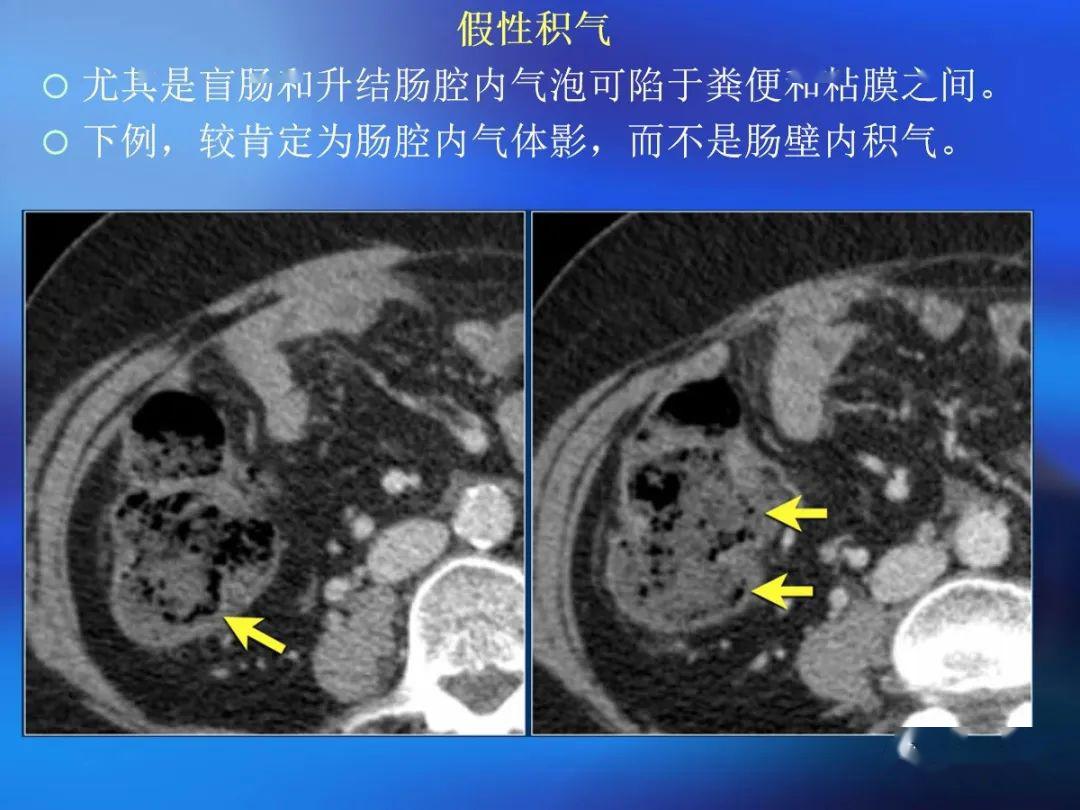

脂肪有时见于乳糜泻ct 评价肠壁增厚存在的问题肠道是蠕动的空腔器官